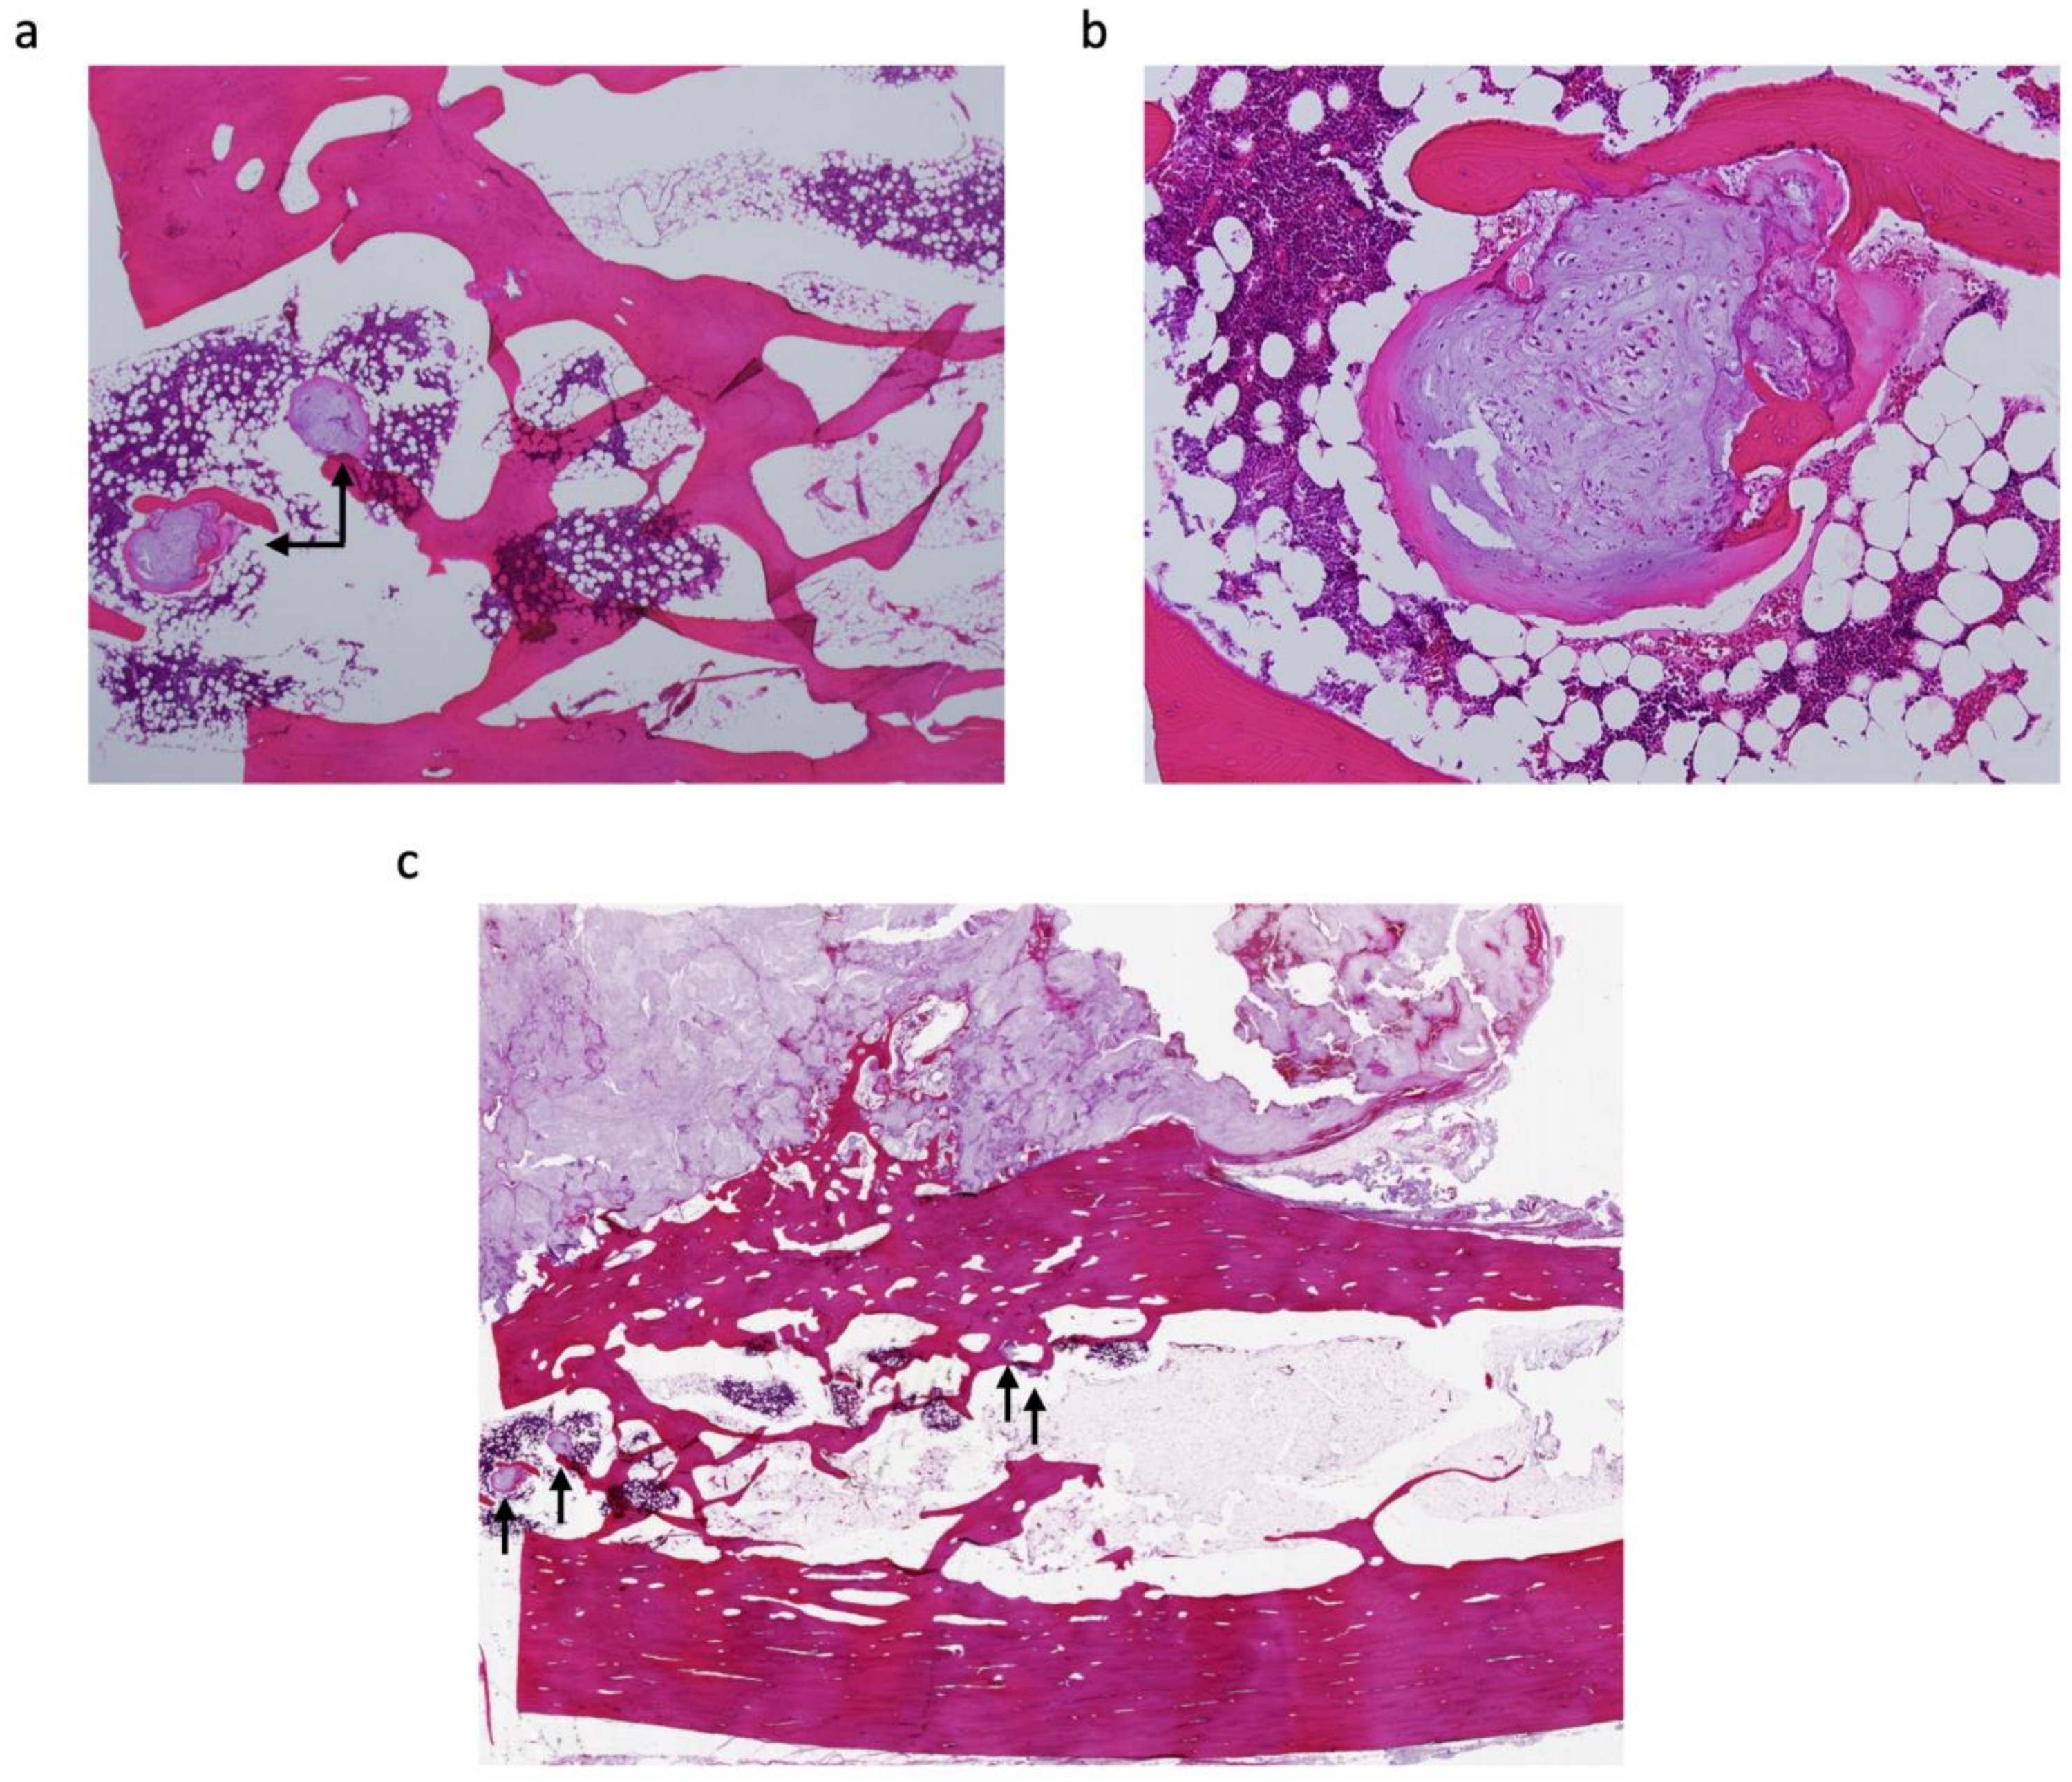

Clinical, Radiological, and Histopathological Characteristics of Periosteal Chondrosarcoma with a Focus on the Frequency of Medullary Invasion

| Case | Medullary Invasion (MRI) | Medullary Invasion (Pathological) | Distance from the Cortex to the Deepest Lesion of the Intramedullary Tumour (mm) | Skip or Continuous from Periosteal Tumour |

|---|---|---|---|---|

| 1 | − | + | 15 | continuous |

| 2 | + | + | 15 | continuous |

| 3 | + | + | 25 | skip |

| 4 | − | + | 3 | skip |

| 5 | + | + | 18 | skip |

| 6 | − | + | 1 | continuous |

| 7 | − | − |